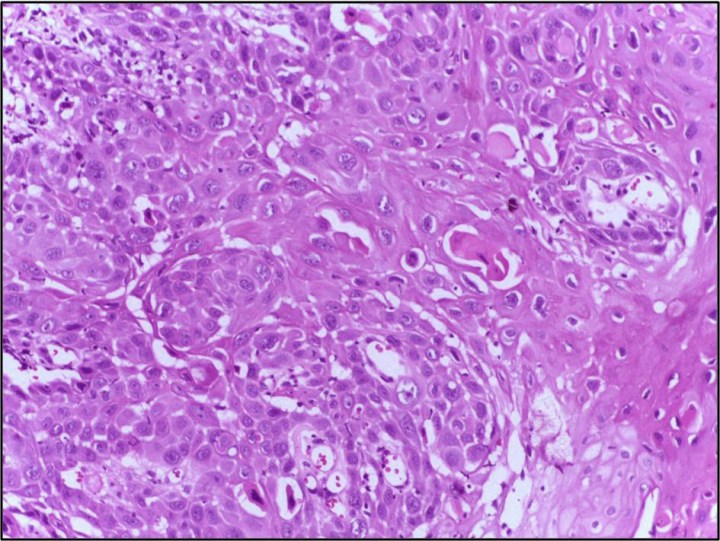

Cutaneous squamous-cell carcinoma is one of the most common skin cancers, and approximately 8500 people died from it as recently as 2012. A majority of patients who are diagnosed with this type of cancer are cured by surgery, but a small percent of patient are not because of metastasis or the tumor being unaffected by surgery. Since some of the markers of this carcinoma seem to be similar to other tumors that can be treated with immunosuppressants, a study was conducted to see if cemiplimab (a monoclonal antibody) can induce lasting change to treat this type of tumor.

- Image retrieved from: https://commons.wikimedia.org/wiki/File:Squamous_cell_carcinoma_skin,_Well_differentiated_40X.jpg